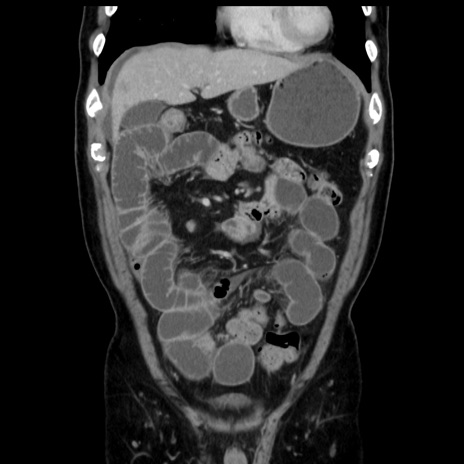

症例16(冠状断像)

【症例】 70歳代男性

【主訴】 腹痛、嘔吐

【現病歴】 約1ヶ月前より間欠的に腹痛と嘔吐あり、当院消化器内科を受診したところCTで多発する肝臓のLDAを指摘され、精査中であった。以降は消化器症状は安定していたが、2日前より嘔気と腹痛があり、同日より排便・排ガスが消失した。改善認めず、 本日、救急外来を受診した。

【既往歴】 大腸ポリープ切除後。

【身体所見】意識清明・会話良好、BT 36.3℃、BP 127/80mmHg、 P 80bpm、腹部:膨満あり、平坦・軟、上腹部正中および下腹部正中に圧痛あり、反跳痛なし、筋性防御なし。

【データ】WBC 7200、CRP 0.77